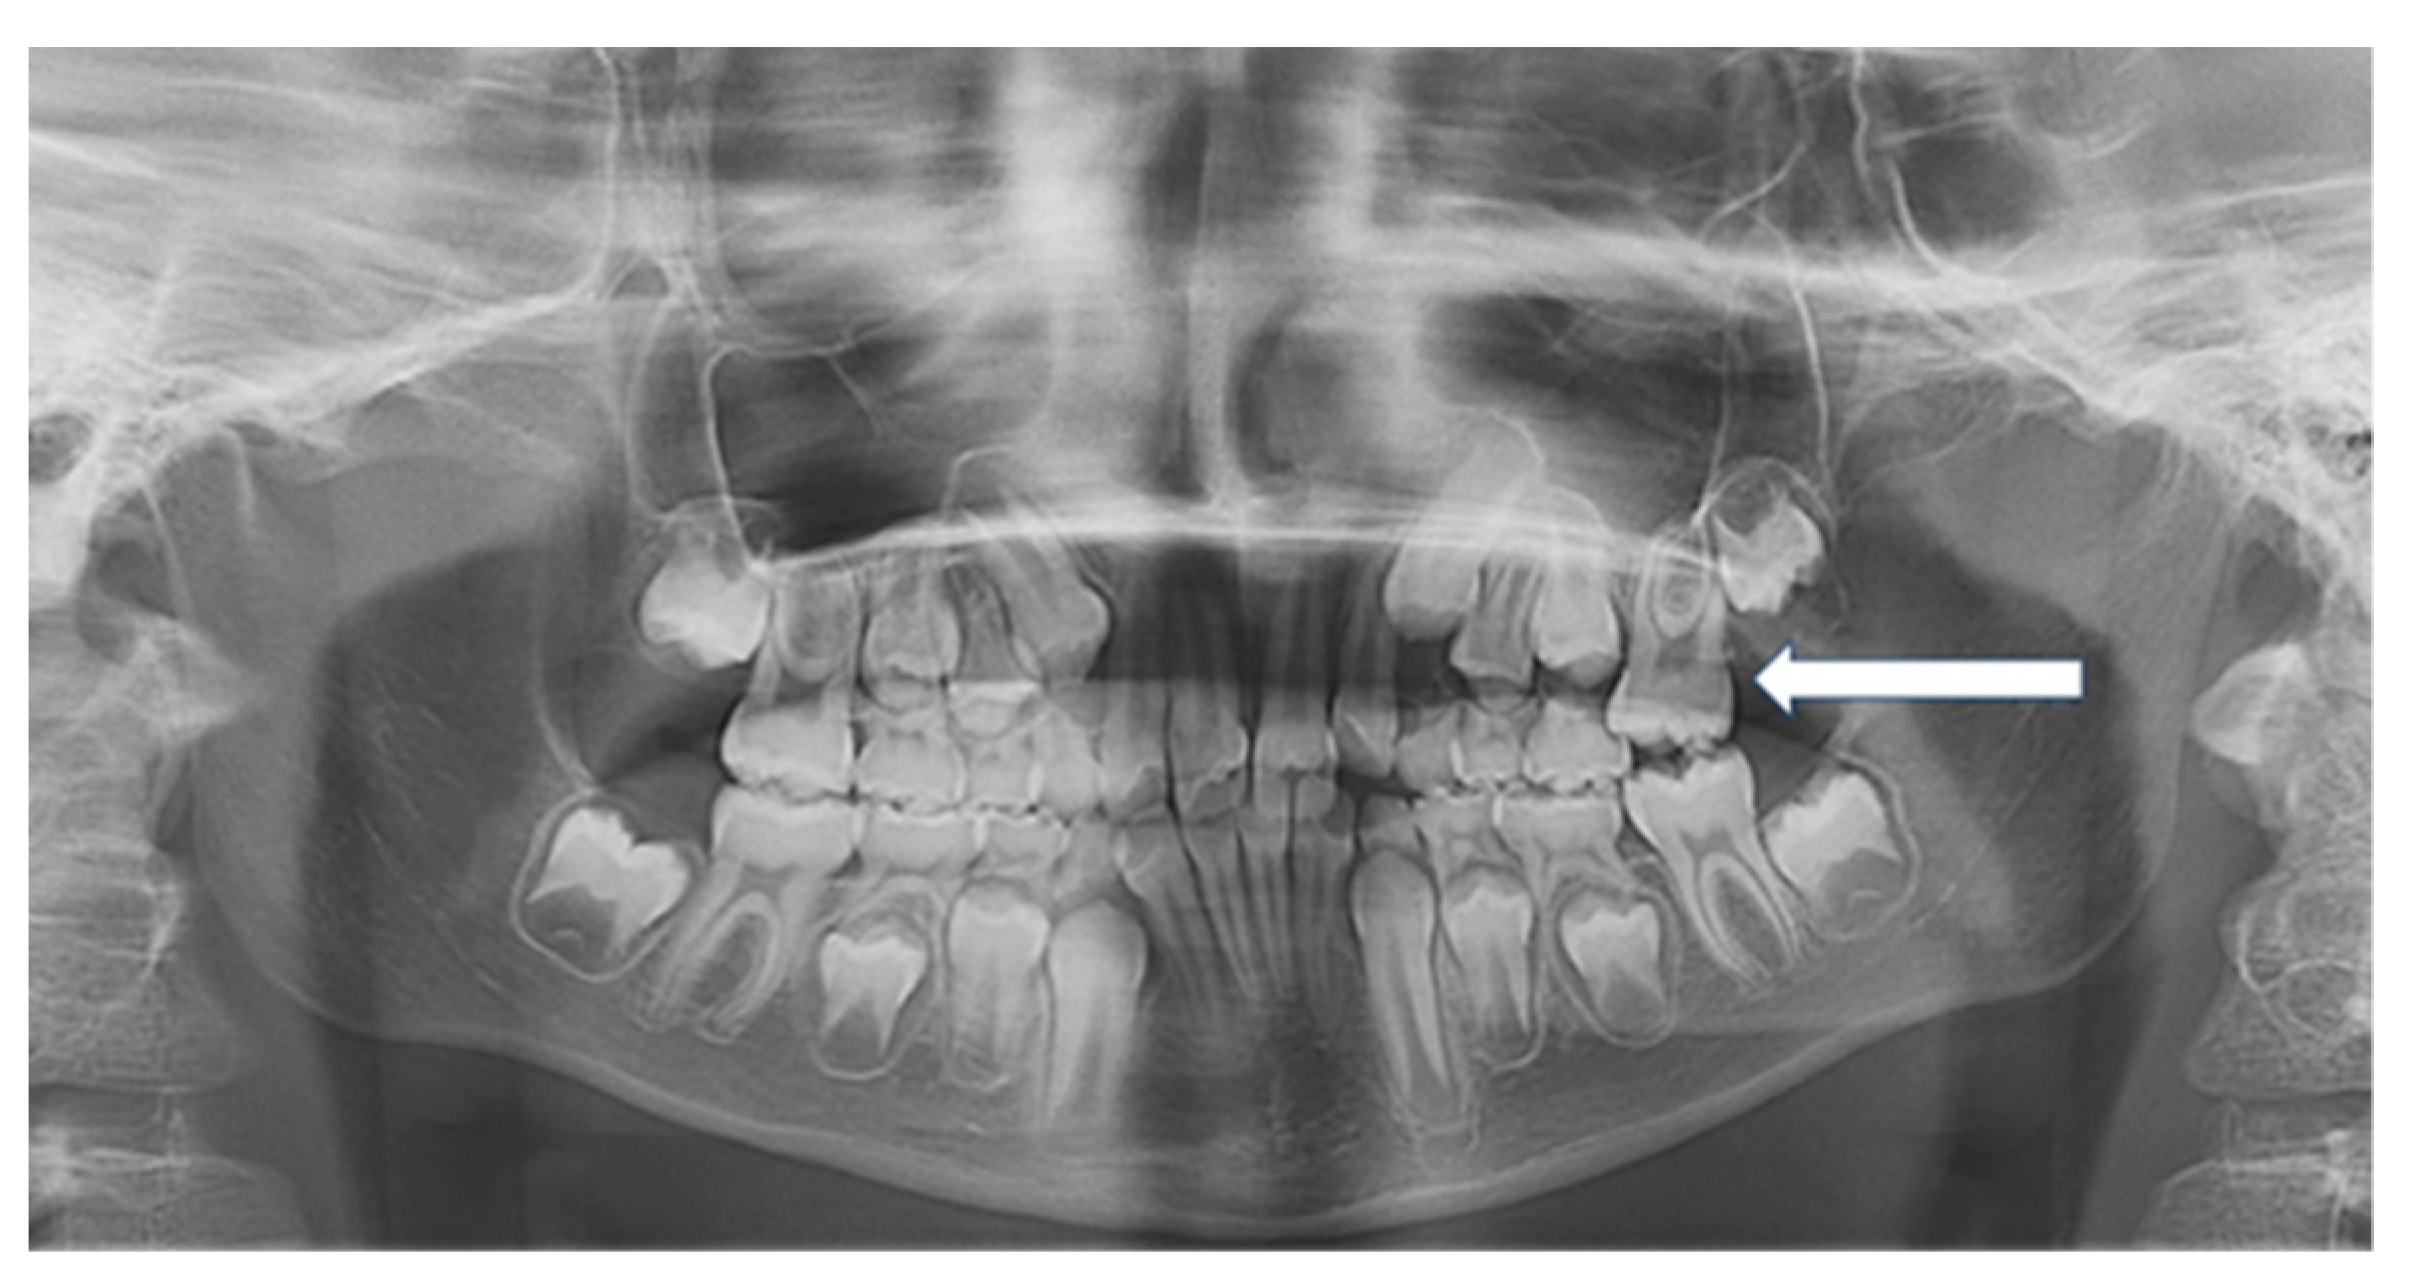

Several orthodontic procedures have been previously proposed [8,17]. The majority of our cases were treated using a rapid palatal expander, cemented to the second deciduous molars and modified with a Halterman spring [18], soldered to the band on the side of the ectopic eruption. An elastic chain was placed from the hook to a bonded button on the occlusal surface of the ectopically erupting permanent molar, as shown in Figure 2 The use of a palatal expander was justified by a clinically evaluated maxillo-mandibular discrepancy in the posterior-transverse diameter, as already reported in the literature [17].

Figure 2. Linear and angular measurements on a lateral cephalogram: distance S-N, distance Ba-S, distance from Snp to A, distance Snp-Sna, distance Go-Me, distance SOR-Sna, distance Sna-Me, Wit’s index, SNA, SNB, ANB (Steiner). Intermaxillary angle: SnaSnp-GoMe. Cranio-mandibular angle: SN-GoMe. Cranio-maxillary angle: SN-SnaSnp.